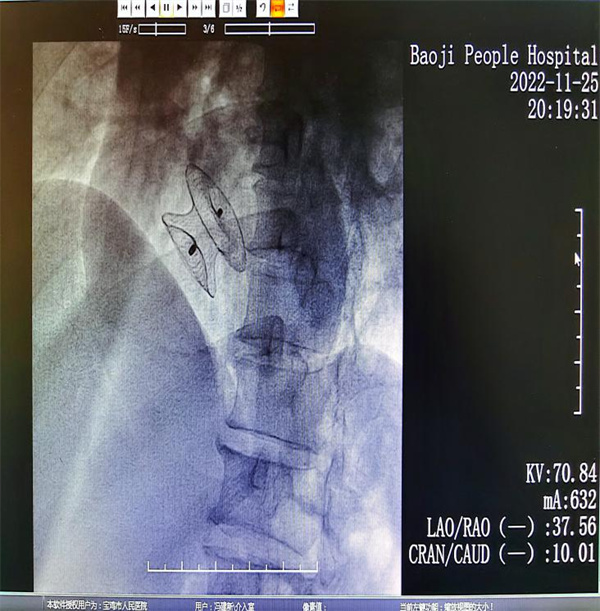

科室经过反复术前谈论,制定了详细的手术策略,征得患者与家属同意,于11月25日在局麻下由郑广生主任、李沫帆主治医师行右心导管检查+房间隔缺损介入封堵术。术中右心导管检查再次证实心房水平存在异常通道,房水平左向右分流,在我院超声科吕品副主任的密切配合下,选取了大小最佳的封堵器,并达到精准释放。整个手术历时不足1小时,术后患者安返病房,未诉特殊不适。术后复查心脏超声未见房间隔瘤样膨出及无房水平分流,目前患者已康复出院。